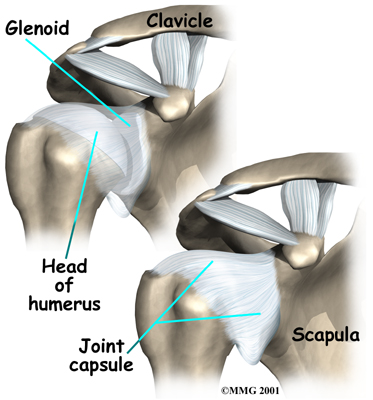

Tendons attach muscles to bones. Muscles move bones by pulling on tendons. The muscles of the rotator cuff also keep the humerus tightly in the socket. A part of the scapula, called the glenoid, makes up the socket of the shoulder. The glenoid is very shallow and flat. A rim of soft tissue, called the labrum, surrounds the edge of the glenoid, making the socket more like a cup. The labrum turns the flat surface of the glenoid into a deeper socket that molds to fit the head of the humerus.

Surrounding the shoulder joint is a watertight sac called the joint capsule. The joint capsule holds fluids that lubricate the joint. The walls of the joint capsule are made up of ligaments. Ligaments are soft connective tissues that attach bones to bones. The joint capsule has a considerable amount of slack, loose tissue, so that the shoulder is unrestricted as it moves through its large range of motion. If the shoulder moves too far, the ligaments become tight and stop any further motion, sort of like a dog coming to the end of its leash.

If your physical therapy program doesn't stabilize your shoulder after a period of time, you may need surgery. There are many different types of shoulder operations that have been developed and used in the past to stabilize the shoulder. Almost all of these operations attempt to tighten the ligaments that are loose. The loose ligaments are usually along the front or bottom part of the shoulder capsule.

The most common method for surgically stabilizing a shoulder that is prone to anterior dislocations is the Bankart repair. In the past, the Bankart repair was done through a large incision made in the front (anterior) shoulder joint. This required damage to a great deal of normal tissue in order for the surgeon to be able to see the damaged portion of the joint capsule. The procedure was difficult and usually involved an attempt to sew or staple the ligaments on the front side of the joint back into their original position.

Once any degenerative tissue and bone spurs are removed, the torn ligaments that stabilize the shoulder are reattached to the bone around the socket of the shoulder, the glenoid. Special devices have been designed to reattach these ligaments. These devices are called suture anchors.

Another surgery to tighten a loose shoulder joint is a procedure called a capsular shift. The lining of any joint is called the joint capsule. The joint capsule forms a pocket, or bag that is made up of the ligaments and connective tissue around the joint. The shoulder joint has a fairly large joint capsule that is necessary to allow the joint to move in such a wide range.

Sometimes the problem causing the shoulder instability is because the joint capsule is simply too large. This is sometimes referred to as a redundant, or patulous joint capsule. This may cause shoulder instability in multiple directions. This is sometimes referred to as multi-directional instability. In order to fix this type of instability, the joint capsule needs to be made smaller and tightened.

This procedure also can be performed using the arthroscope. The surgeon pulls the flap of tissue over the front of the capsule and connects it together. This is similar to when a tailor tucks loose fabric by overlapping and sewing the two parts together. Once the appropriate degree of tightness is achieved, the surgeon uses a combination of sutures and suture anchors to hold the joint capsule in this position until healing occurs.